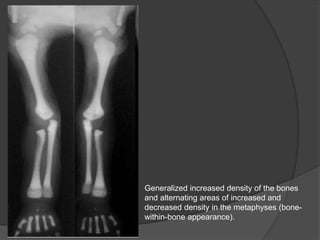

Generalized increased density of the bones

and alternating areas of increased and

decreased density in the metaphyses (bone-

within-bone appearance).